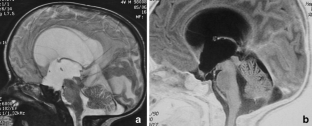

The sylvian aqueduct is the most common site of intraventricular blockage of the cerebro-spinal fluid. Clinical aspects, neuroradiological appearance, and treatment of hydrocephalus secondary to aqueductal stenosis are specific.

The correct interpretation of the modern neuroradiologic techniques may help in selecting adequate treatment between the two main options (third ventriculostomy or shunting). In the last decades, endoscopic third ventriculostomy has become the first-line treatment of aqueductal stenosis; however, some issues, such as the cause of failures in well selected patients, long-term outcome in infant treated with ETV, and effect of persistent ventriculomegaly on neuropsychological developmental, remain unanswered.